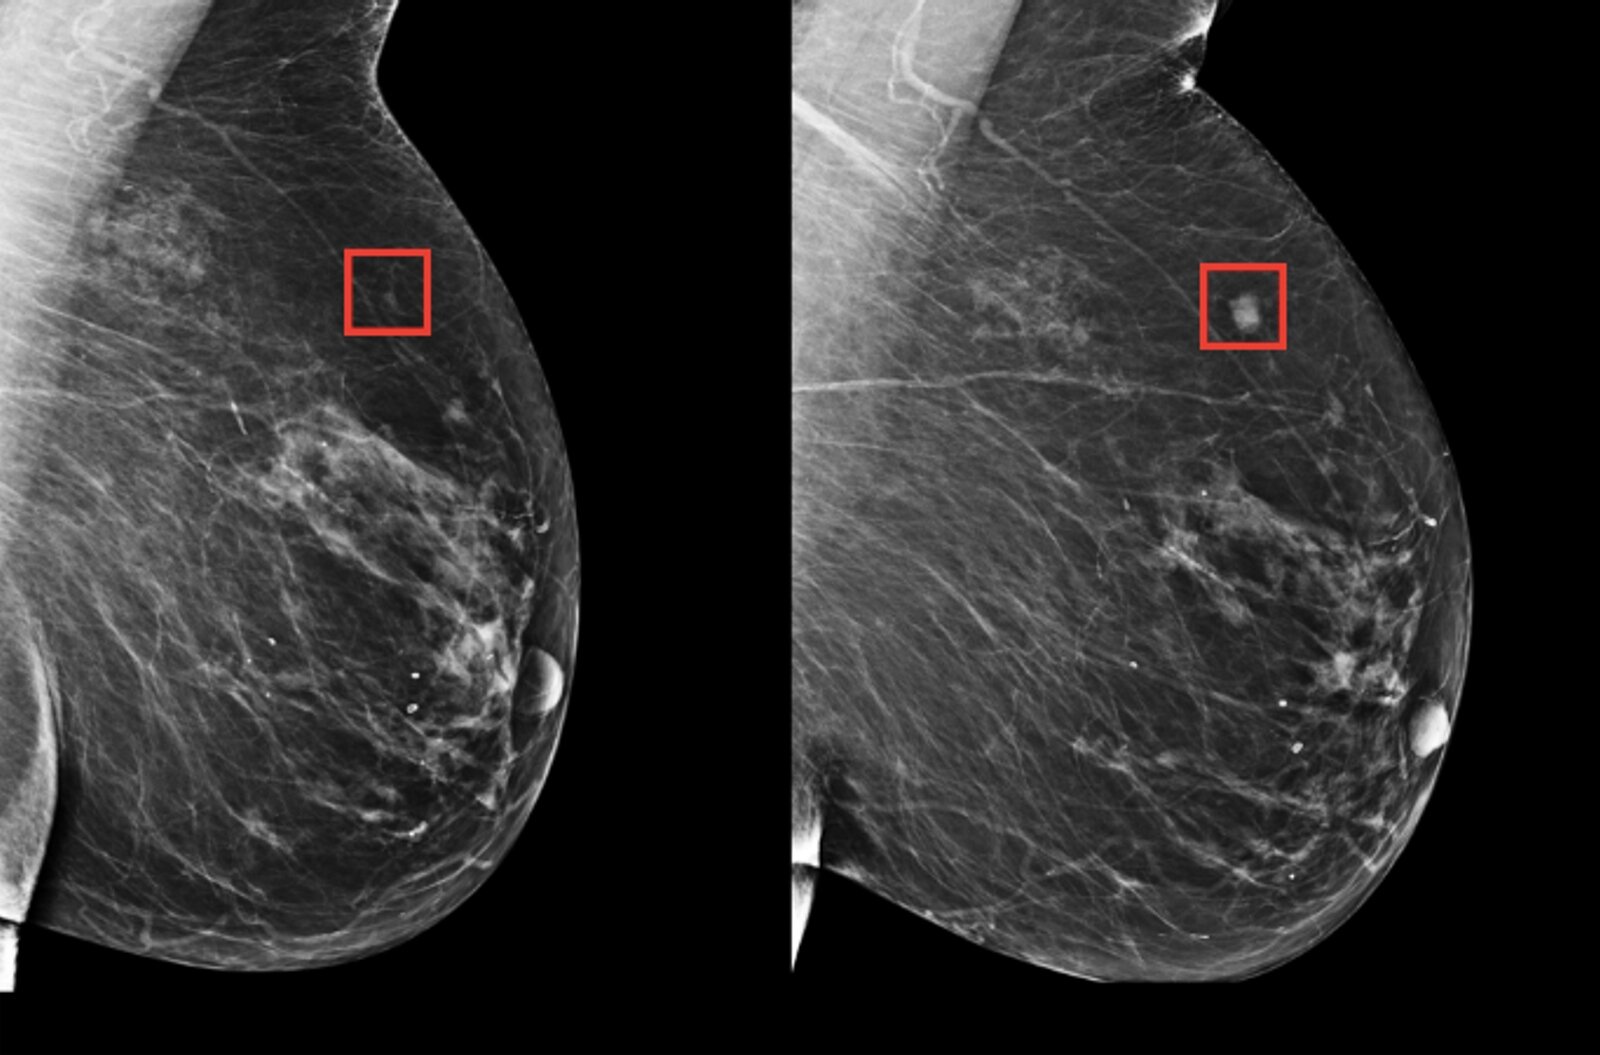

Estudios anteriores estimaban que hasta 30% de los cánceres detectados después de una mamografía negativa ya estaban presentes, pero no fueron identificados en ese momento. Con este antecedente, investigadores y médicos han entrenado sistemas de IA para mejorar la lectura de las imágenes y detectar lesiones difíciles de apreciar.

Aun así, no estaba claro si el uso de IA realmente reduciría los cánceres diagnosticados entre controles. Para aclararlo, el nuevo estudio incluyó a más de 100,000 mujeres en Suecia que fueron asignadas aleatoriamente a dos grupos: uno con mamografías asistidas por IA y otro con el método tradicional, en el que dos radiólogos evaluaban cada imagen. Las pruebas se realizaron entre abril de 2021 y diciembre de 2022.

El sistema de IA empleado había sido entrenado con más de 200,000 estudios previos procedentes de hospitales en más de 10 países. Los resultados mostraron que el 81% de los casos de cáncer en el grupo con IA se detectaron durante el cribado, frente al 74% en el grupo convencional.

Entre una revisión y otra, se identificaron aproximadamente 1.55 casos por cada 1,000 mujeres en el grupo con IA, comparado con 1.76 por cada 1,000 en el grupo estándar. Además, los tumores en el grupo asistido por IA tendían a diagnosticarse en fases más tempranas y tratables. En comparación con el método tradicional, hubo 16% menos cánceres invasivos, 21% menos tumores de gran tamaño y 27% menos casos agresivos.